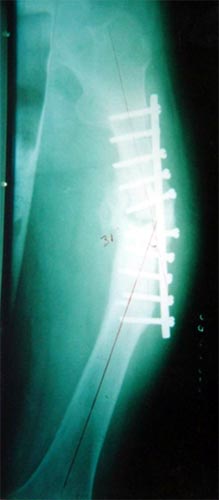

病例三、患者42岁,股骨中1/3骨折骨不连2年,钢板手术失败,明显畸形。

采用上述方法成功治愈。